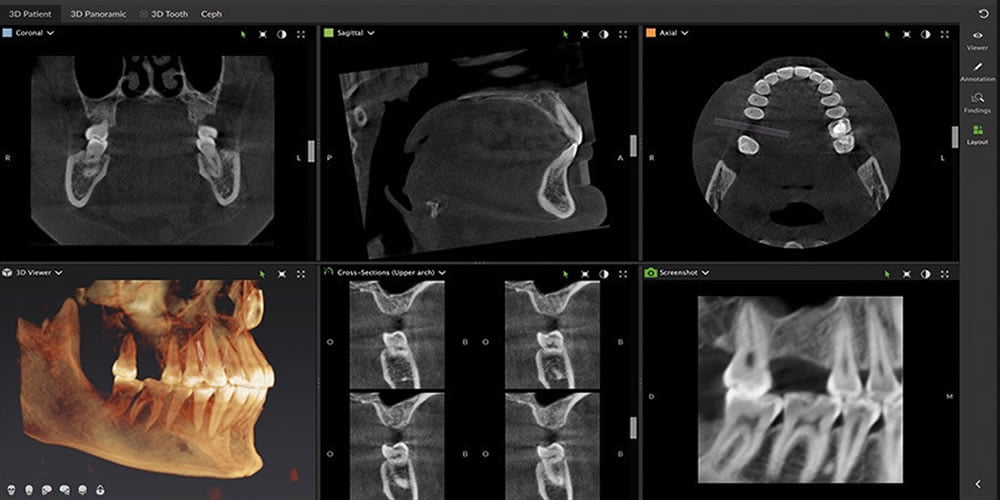

- Diş sağlığı ve diş yapısı ile ilgili bir gülümseme analizi ile doğrulanan belirli yönlerin mevcut olması gerekir.